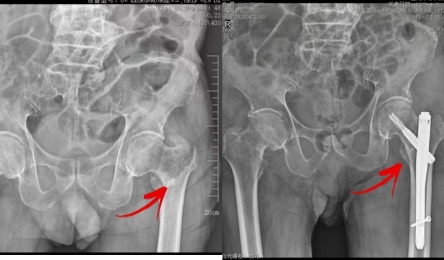

• 直击“医”线|94岁老人股骨粗隆间骨折,还合并多种慢病……

高龄就一定是“手术禁区”吗?未必!特别是高龄老人骨折后,应予以充分评估,符合手术条件的,应尽早手术,从而让患者尽快恢复,减少并发症,降低死亡率。       有一名94岁老人,在家时不慎摔...